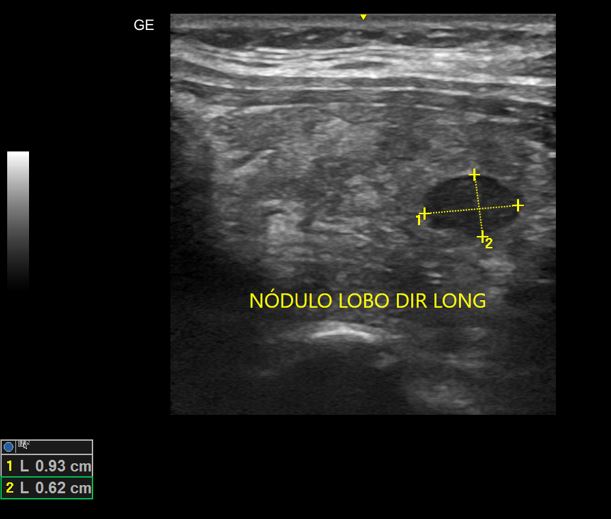

Nódulos de Tireoide

USG de nódulos benignos